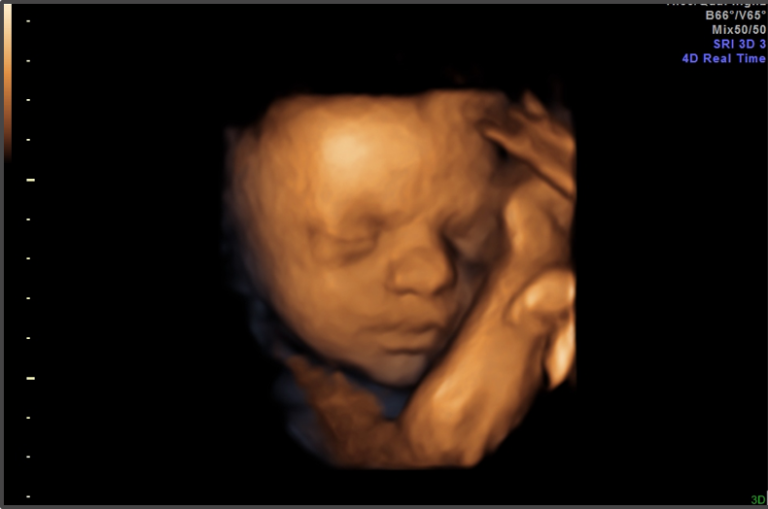

“The science is clear and real; There are things only women can do, like perform the miracle of birth,” Sanders wrote in the executive order shared first with Fox News Digital. “Government should reject language that ignores, undermines, and erases women; Government should celebrate gender distinctions between men and women โ€” not erase them.”